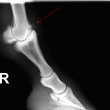

Fragment na spěnkové kosti